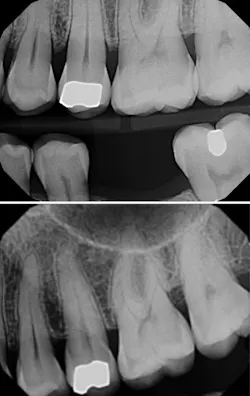

For indirect restorations and restorative foundation codes, a preoperative radiograph is generally required. Notice that the requirement is a radiographic image, not an intraoral photographic image. Some carriers require this preoperative radiograph to be a periapical and some require a periapical x-ray capturing the entire apex to facilitate complete radiographic evaluation of the tooth’s apex and surrounding tissues.

The clinical claim reviewer is looking to confirm that the apical region is free of pathology and being treated appropriately, which can be documented with a final endodontic radiograph for greatest success, or, at minimum, in the narrative. Since capturing the apex does not give us a complete snapshot of the health of the tooth, the clinical crown needs to be evaluated, and this is done either by capturing the coronal structure in the same PA or by providing additional radiographs, more PAs, or, more commonly, a bitewing.

Sometimes, offices provide intraoperative photos and/or radiographs, but these do not meet preoperative radiograph requirements. A common scenario for confusion, resulting in a request for more information, an adverse determination such as a denial, or an appeal, is a case involving a dislodged crown. The PA acquired prior to registering a new impression or scan is preoperative and should be communicated in a narrative. During my peer-to-peer calls, offices would tell me, “The claim form says the prior date for treatment was xx/xxxx,” but without the indication that the crown was lost and the radiograph enclosed is preoperative, a consultant will assume a crown was in place and removed before acquiring the x-ray, which would make the x-ray intraoperative. It’s best to communicate the tooth’s story in your narrative.

If you chose to submit a truly intraoperative photo and/or radiograph, consider what you are trying to demonstrate, remembering that the insurance carrier is not looking to confirm treatment was done but to establish medical necessity for the tooth at the time of treatment. On these peer-to-peer calls, patients would tell me the photos demonstrate the little remaining tooth structure after the filling was removed, but many clinical claim reviewers will say this may be due to an overzealous preparation design. My perspective is that it may be better to capture images of the decay under the filling that was removed, rather than the state of the final preparation.